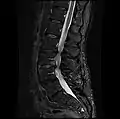

MRI lumbar spine with degeneration, post-hemilaminectomy L4-5 (sagittal T1 FSE)